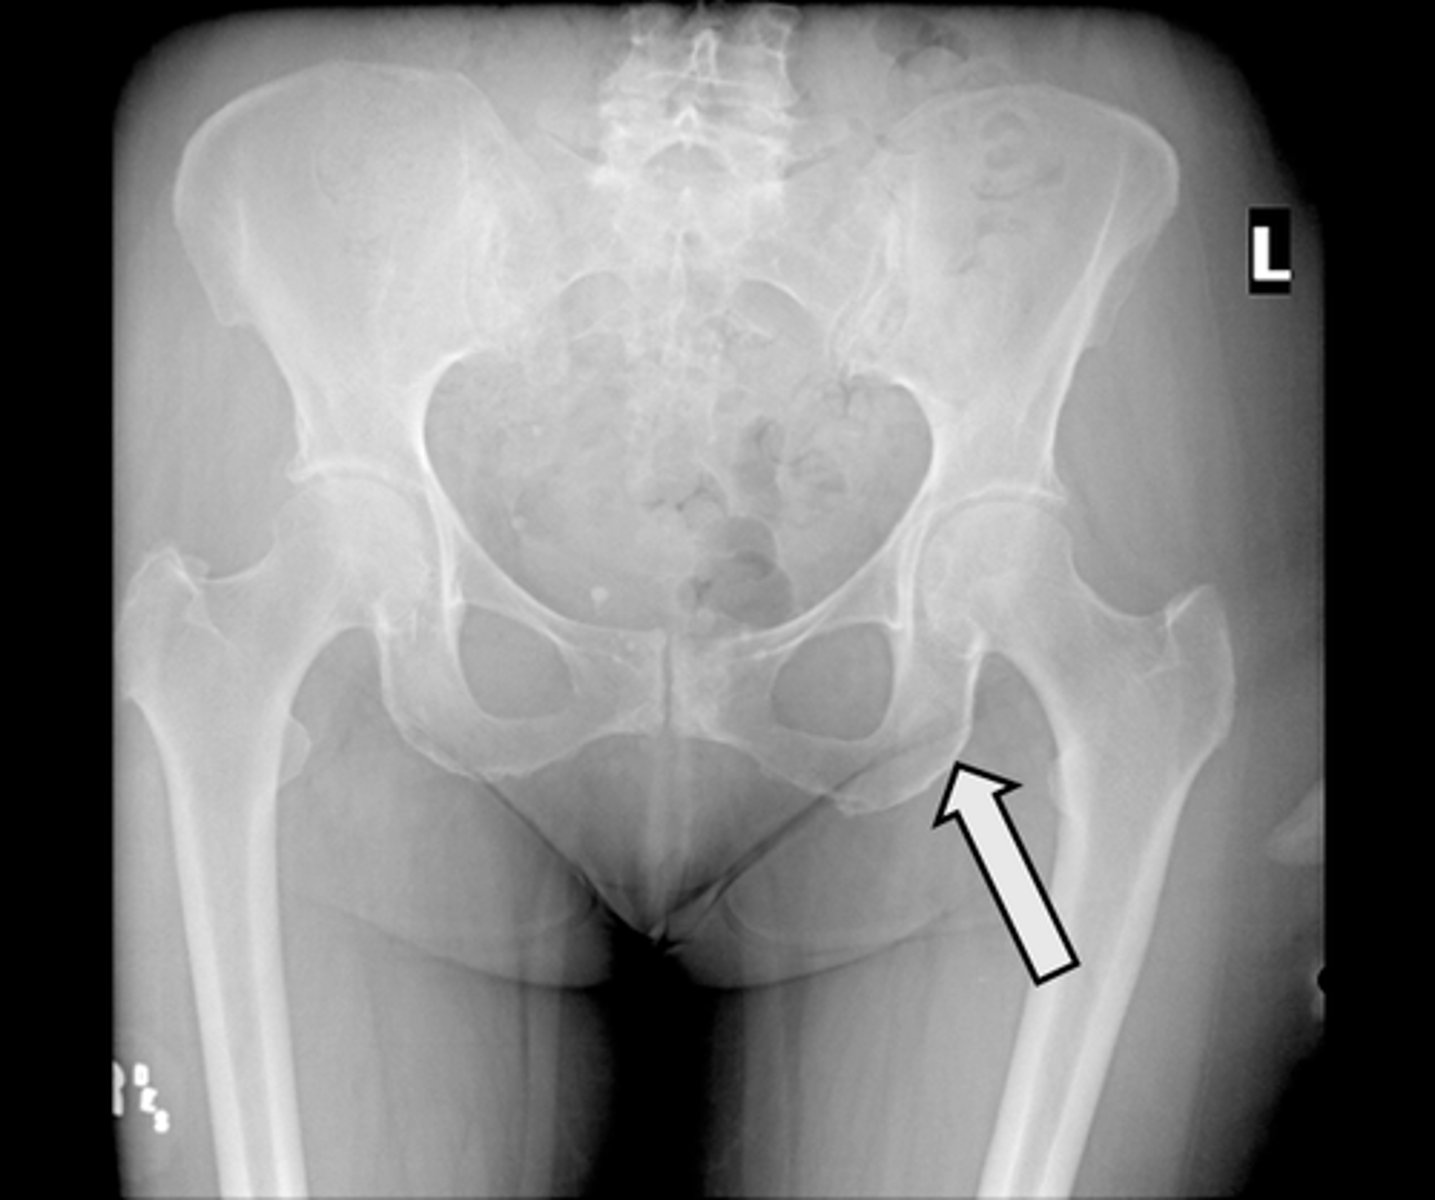

AP pelvis

What is the image?